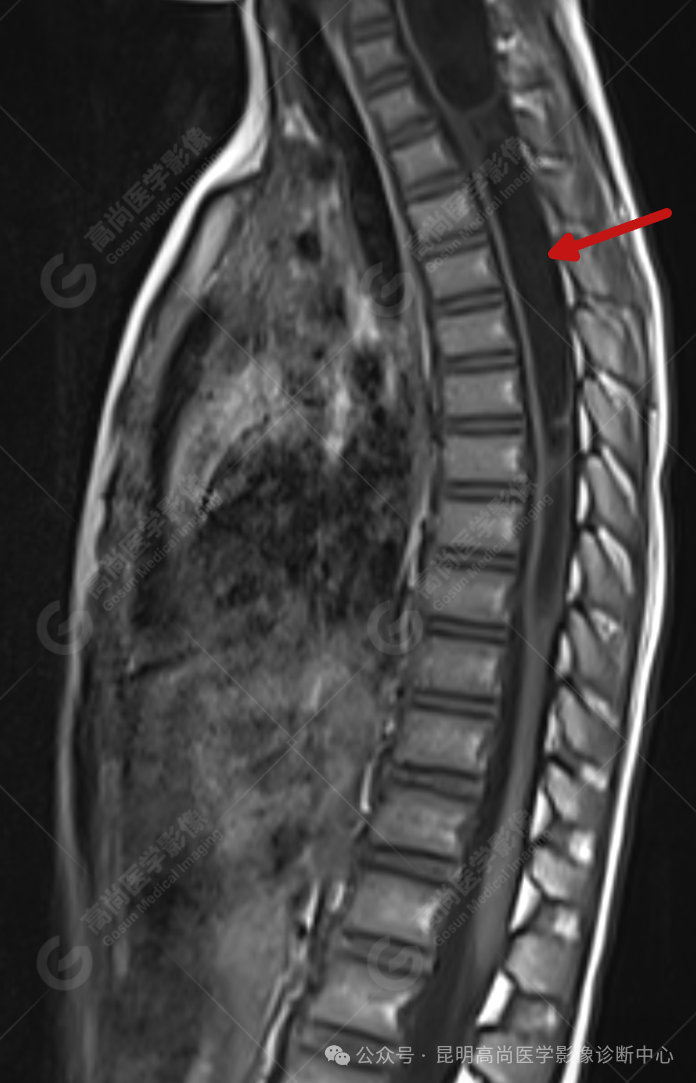

颈 3-5 层面颈后部软组织不规则片状异常信号影,脊膜膨出可能;颈 3、4 棘突局部显示不清;颈胸髓内(约颈 3-胸 9 椎体水平)异常信号影,考虑囊肿并局部颈髓空洞可能,肿瘤或其他待排;请结合临床及相关检查。